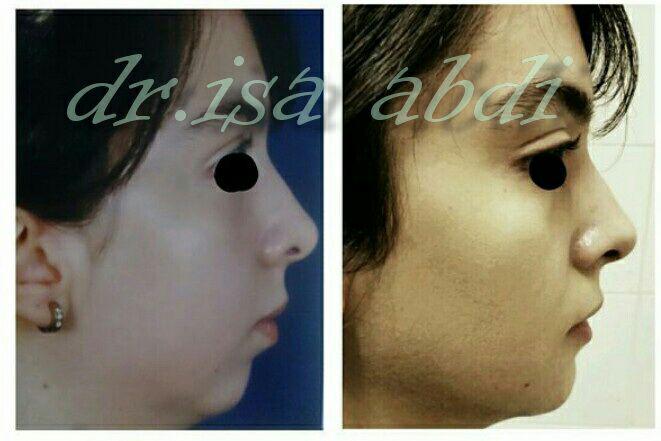

دکتر عیسی عبدی در رشت

– متخصص جراحی فک , پلاستیک صورت و بینی

جراحی فک , پلاستیک , صورت وبینی

جراحی ترمیمی و زیبایی فک و صورت و جمجمه و گردن